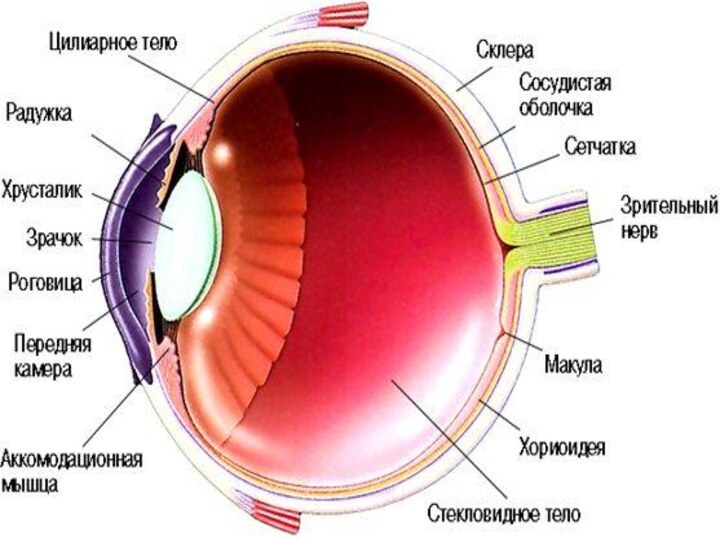

КТ-графики и изображение строения глаза